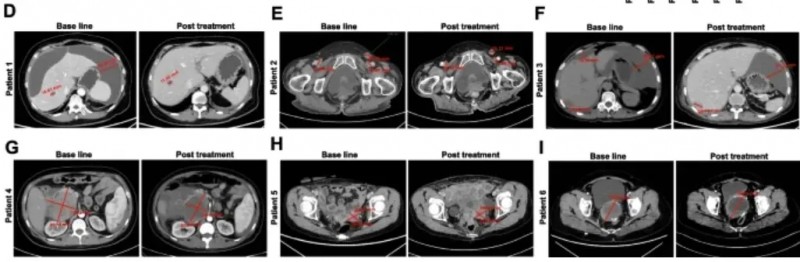

更值得关注的是,该疗法部分缓解率达33.3%:2例患者实现“部分缓解”(肿瘤缩小≥30%),其中患者1肝转移灶缩小31%且腹腔积液消失,患者2可测量病灶总最大直径缩小42%。

国研CEA CAR-T精准狙击"癌细胞特供"靶标!70%结直肠癌患者获病情稳定,最长持续超7.5个月

该研究共纳入10例转移性结直肠癌(CRC)患者,中位年龄58岁(范围48.8-67岁),其中80%(8/10)伴肝转移、50%(5/10)伴肺转移,所有患者入组后均接受CEA CAR-T细胞静脉输注。

结果显示:10例既往治疗进展(PD)的患者中,7例经CAR-T治疗后达病情稳定(SD),肿瘤直径仅轻微变化,其中P3、P5患者稳定期超30周(7.5个月)。